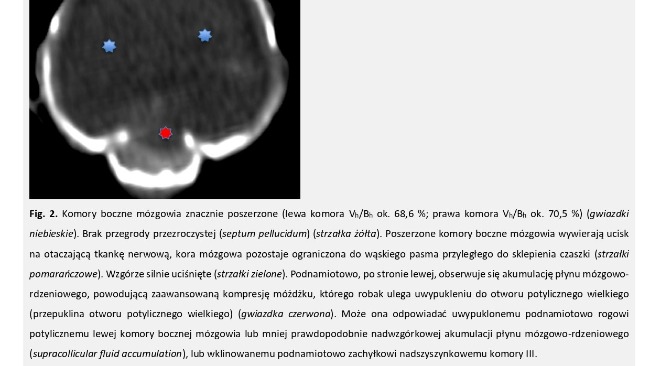

Poniżej opis tomografii komputerowej.